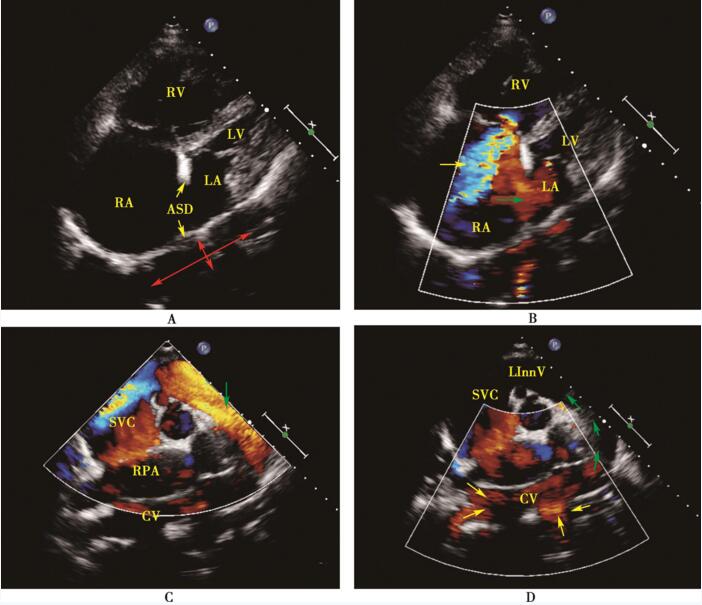

患者入院后给予间断吸氧、卡托普利降肺动脉压治疗。入院3天后复查超声心动图:右心房、右心室重度扩大,左心房、左心室偏小;主肺动脉内径增宽;房间隔继发孔处近房顶可见回声缺失2.6cm,未见肺静脉回流入左心房,左心房后上方见一长管形共同腔,四支肺静脉均汇入此腔(6.3cm×2.0cm),向上发出垂直静脉,连接于左无名静脉;左无名静脉连接上腔静脉,形成一静脉弓,左无名静脉、上腔静脉明显增宽。彩色多普勒:中度三尖瓣反流,连续多普勒估测肺动脉收缩压67mm Hg,房间隔继发孔处探及右向左为著的双向分流;较细的动脉弓升支段呈红色,降支段呈蓝色;粗大的静脉弓右侧呈蓝色为上腔静脉,垂直静脉与左无名静脉彩色血流显像均呈红色 (图42-1)。结论:先天性心脏病,完全性肺静脉异位引流 (心上型),房间隔缺损 (继发孔),中度肺动脉高压。

图42-1 术前超声心动图

A:心尖四腔切面二维图像示右心房、右心室明显增大,继发孔房间隔缺损,未见肺静脉回流入左心房,左心房后上方见一长管形共同腔 (红箭头所示); B:心尖四腔切面彩色多普勒示中度三尖瓣反流 (黄箭头所示),房间隔水平右向左分流 (绿箭头所示); C:胸骨上凹主动脉横切面彩色多普勒显示共同腔发出垂直静脉 (绿箭头所示)与左无名静脉相连,后汇入粗大右上腔静脉,形成一静脉弓; D:胸骨上凹切面彩色多普勒显示四支肺静脉 (黄箭头所示)均汇入共同腔,共同腔发出垂直静脉 (绿箭头示其内血流方向)与左无名静脉相连后汇入粗大右上腔静脉,形成静脉弓。RA:右心房;RV:右心室;ASD:房间隔缺损;LA:左心房;LV:左心室;CV:共同腔; RPA:右肺动脉;SVC:上腔静脉;LInn V:左无名静脉